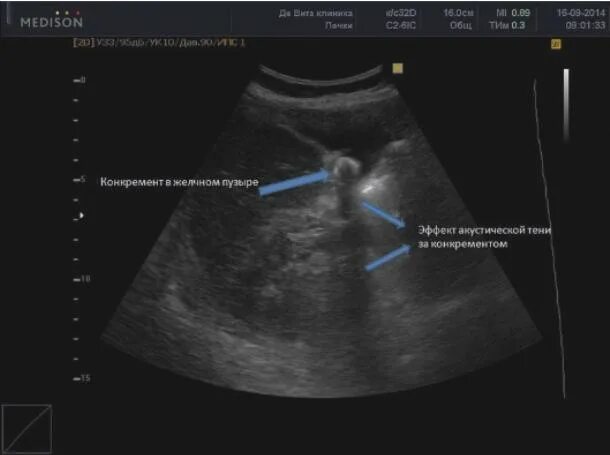

Узи желчного пузыря подготовка к процедуре